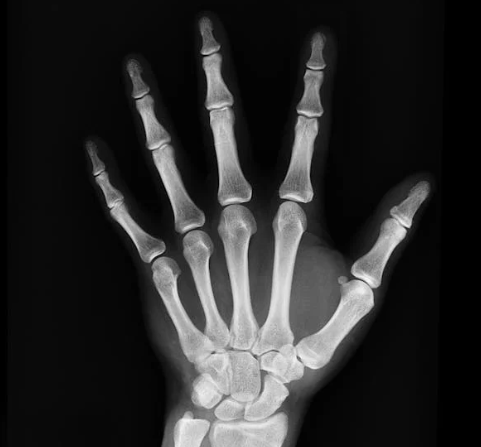

엑스레이, 몇 번까지 찍어도 안전할까?

엑스레이, 몇 번까지 찍어도 안전할까? 방사선 노출 기준 알아보기

병원에서 건강검진이나 진료를 받다 보면 “엑스레이를 자주 찍어도 괜찮을까?” 하는 궁금증이 생기곤 합니다. 특히 치과, 정형외과, 내과 진료에서 엑스레이(X-ray) 촬영은 흔히 시행되는 검사 중 하나이죠. 하지만 방사선이라는 단어만 들어도 왠지 몸에 해롭지 않을까 걱정이 앞서기도 합니다.

왜냐하면 의료 목적의 방사선 검사는 위험보다 이득이 훨씬 크기 때문입니다. 예를 들어, 폐렴을 조기에 진단하거나 골절 부위를 확인하지 못하면 건강을 해칠 수 있는데, 엑스레이 검사는 이 문제를 빠르게 발견해 치료 기회를 제공합니다.